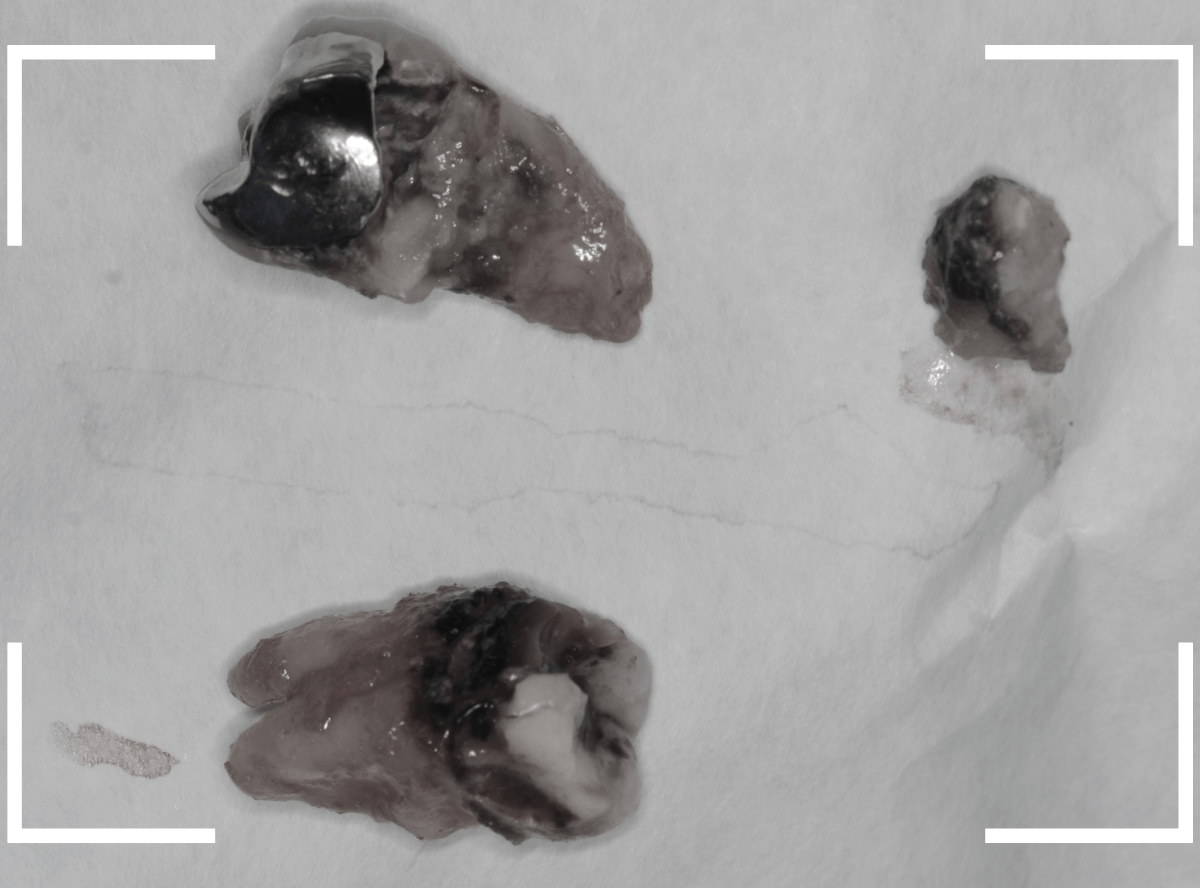

こちらが、抜歯後の写真です。

ここまで虫歯が進行していると、虫歯の治療をしても、ほとんど歯は残っていなかったでしょう。

歯の頭が無くなってしまうと、抜歯も困難にな行ってしまいます。

少しでも虫歯が進行しないうちに、と抜歯を行いましたが、やはりかなり手こずりました。

こちらが抜歯後のおやしらずの写真です。

根だけの状態になっていました(残根といいます)が、こちらは苦労なく抜歯できました。

抜歯した手前の歯をお見せして、

「半年くらい前に受診していたら、歯を残せたかもしれない」というお話をすると、残念がっていました。